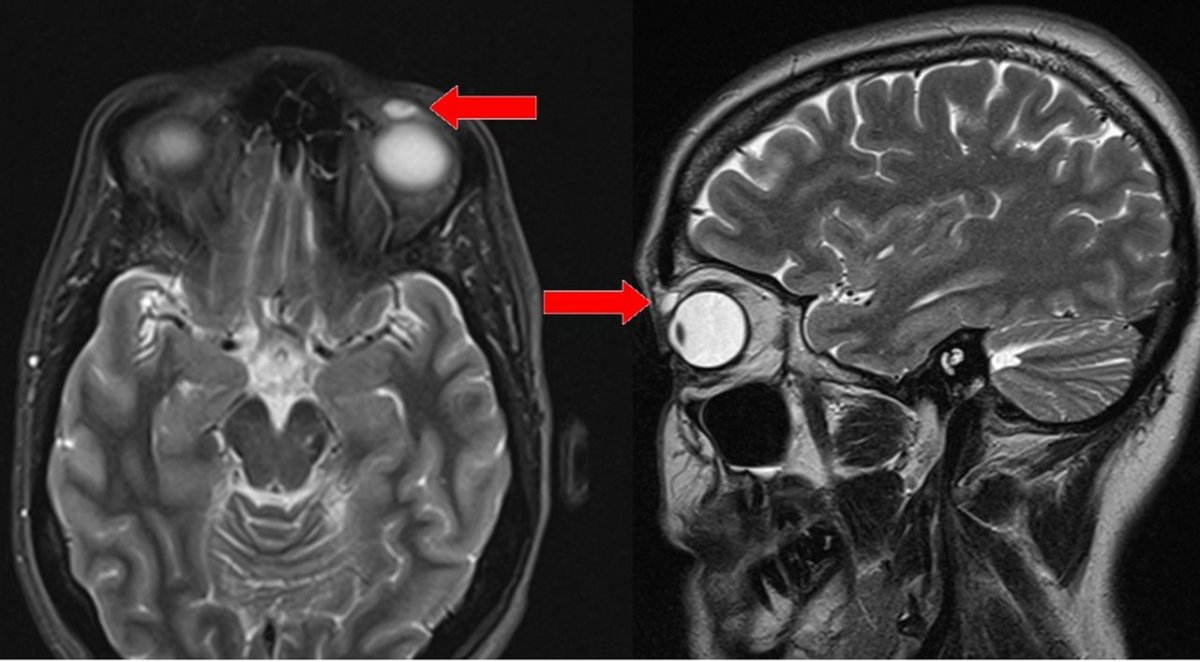

Doctors took an MRI scan to try to figure out what it was. The scan clearly showed a lump of some kind above her eye, with characteristics consistent with a cyst. So, they decided to do surgery to remove the lump.

As surgeons tried to remove the cyst, it ruptured. Inside was a contact lens.